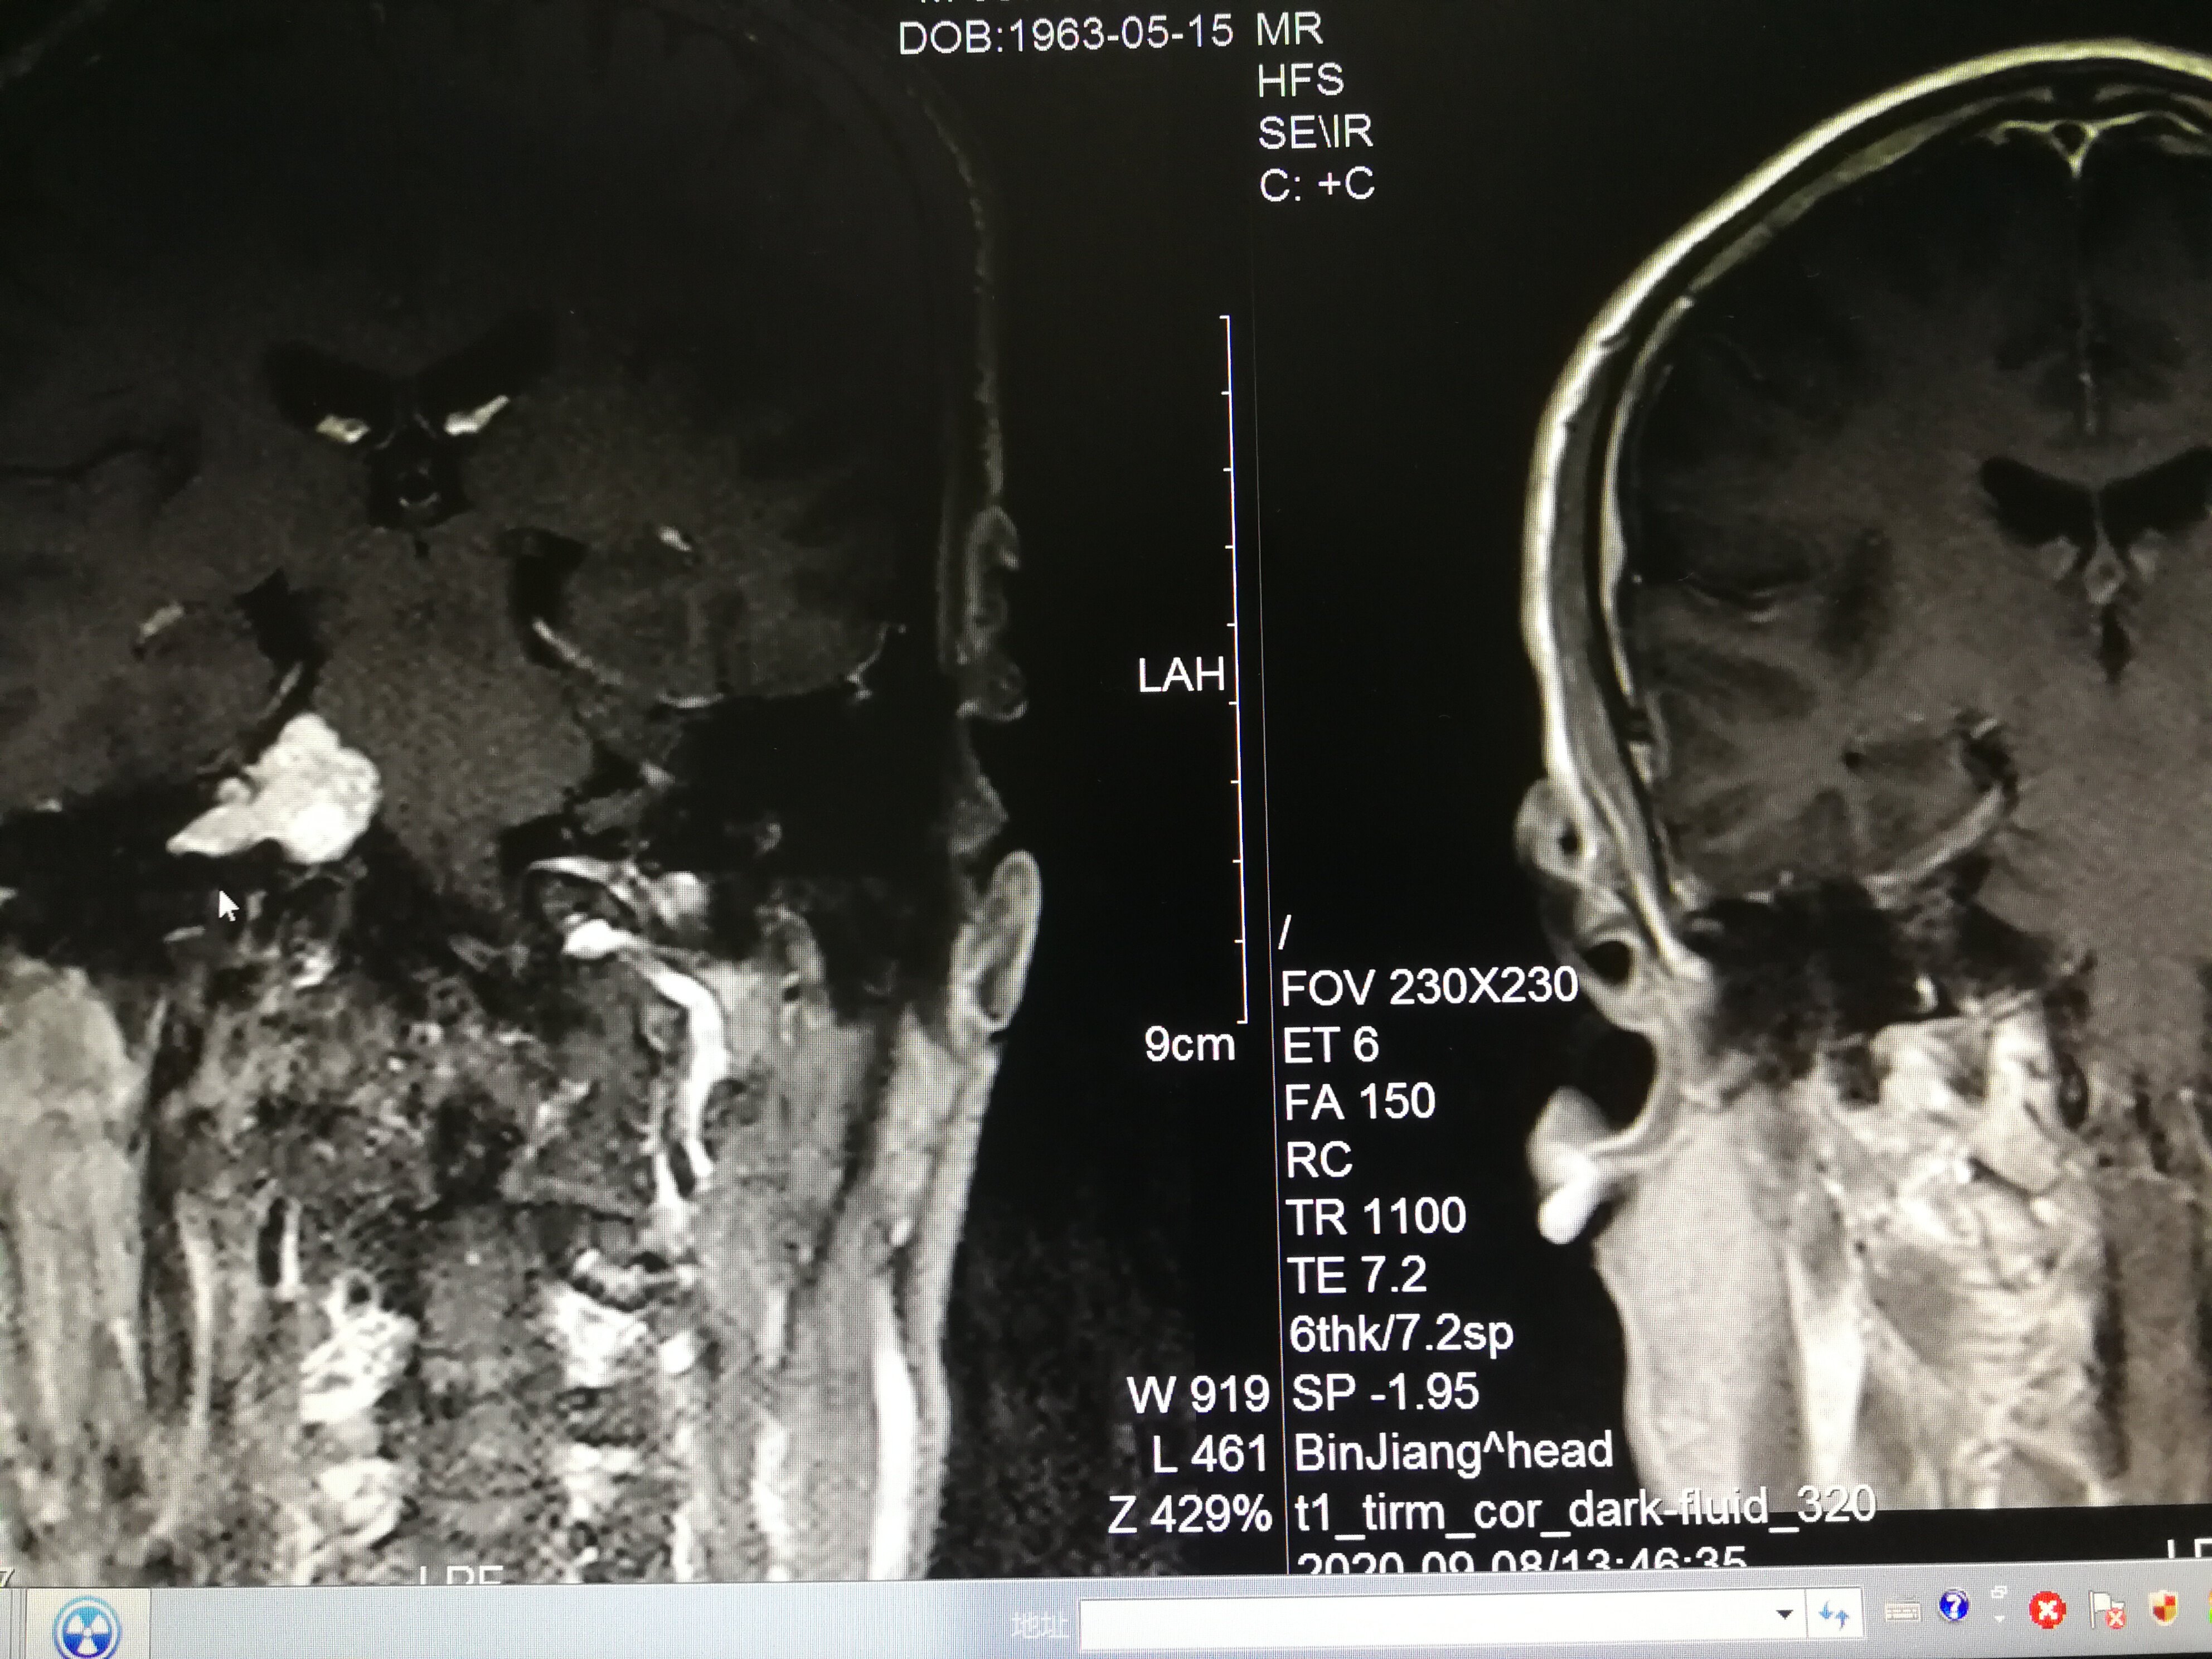

手术治疗听神经瘤是最主要的治疗方式,目前听神经瘤的手术已经非常成熟,只要没有明显的手术禁忌症首先应考虑手术治疗,并要求在电生理监测条件下完成手术,这样可以最大限度地保护面神经功能。以下是几例我们做的听神经鞘瘤手术前后核磁共振片子对照,除手术后听力不能恢复外,没有面瘫,脸部麻木,吞咽困难等颅神经症状,也无其他较明显的手术并发症发生。